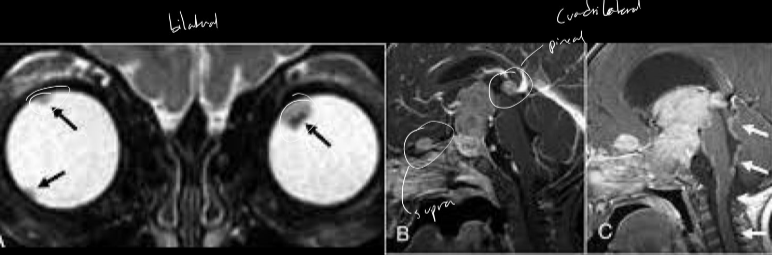

Retinoblastoma

A

Tumor maligno primario de la retina

- Trilateral: bilateral + t. neurplastico (g. pineal)

- Cuadrilateral: bilateral + t. pineal y region supraselar

- Clx: leucocoria - pupila blanca

Estudio de imagen retinoblastoma

Calcificaciones intraoculares

- TC: ver calcificaciones

- RM: mapeo del tumor

- US: ultima opcion si no hay tc o rm